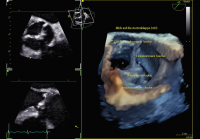

Aortenklappeninsuffizienz: Was gibt es Neues? // Aortic valve regurgitation – What do the 2021 guidelines say? What has changed from 2017?

Journal für Kardiologie - Austrian Journal of Cardiology 2024; 31 (5-6): 120-128 Volltext (PDF) Summary Abbildungen